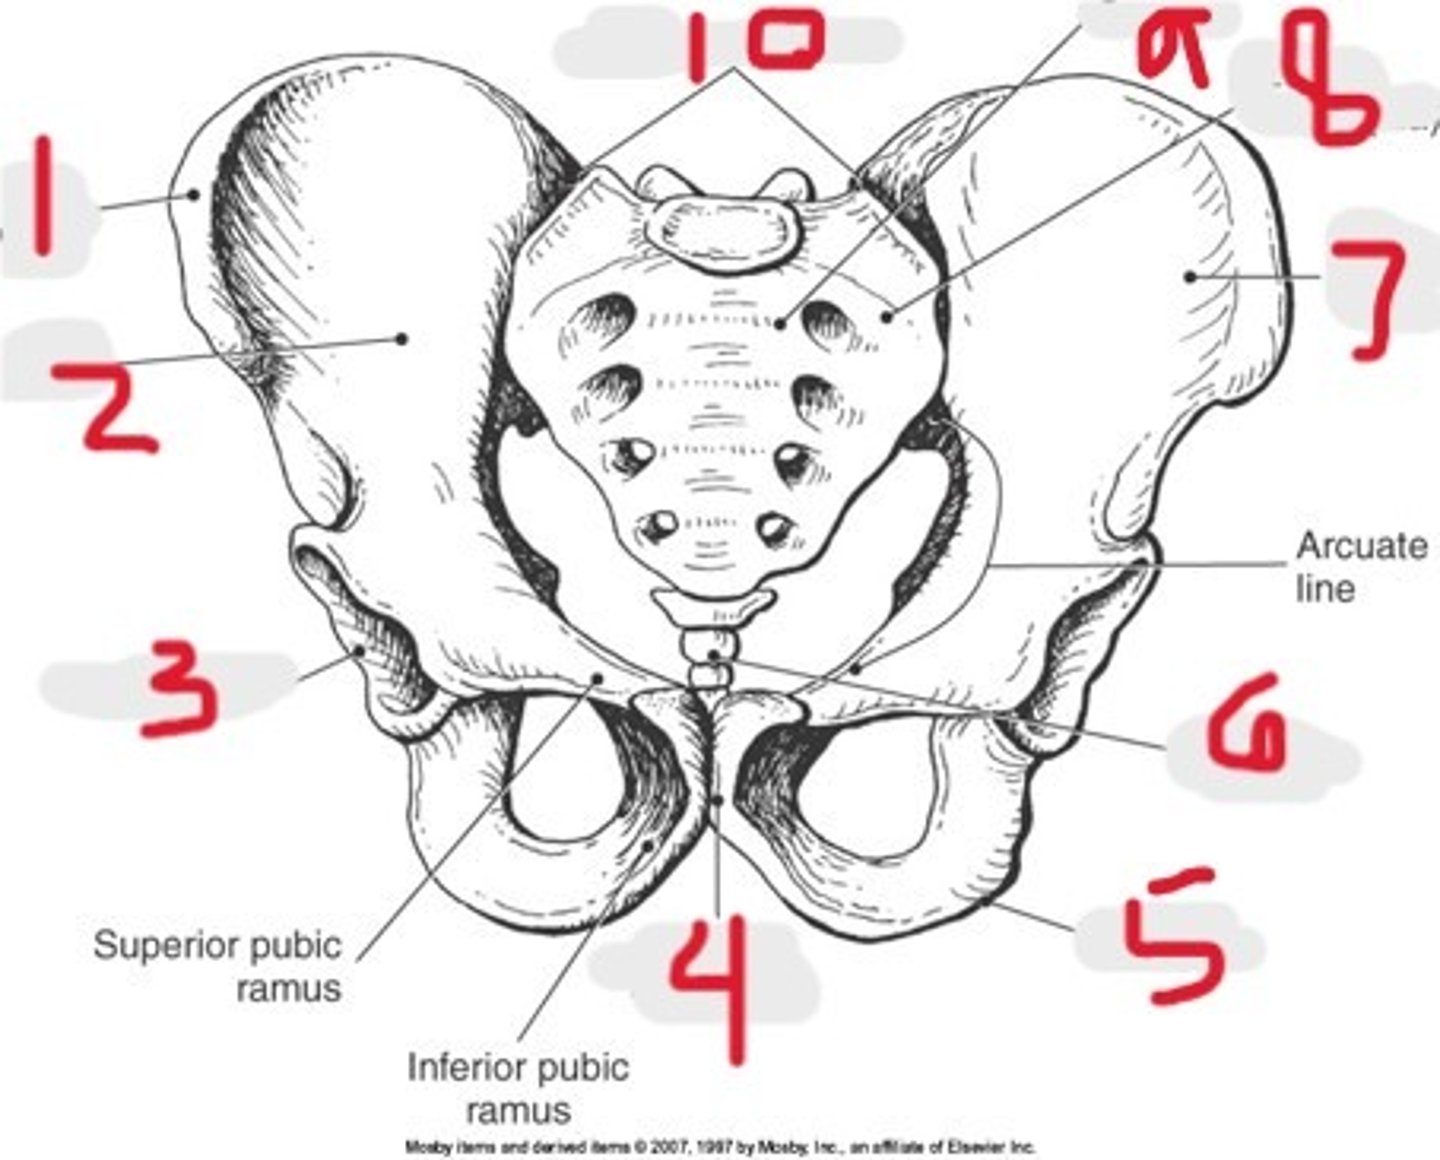

1) Iliac crest

2) Ilium

3) Acetabulum

4) Pubic symphysis

5) Ischium

6) Coccyx

7) Ala of ilium

8) Lateral mass (ala)

9) Sacrum

10) SI joints

Name all numbered structures

1) Ilium

2) Ischium

3) Pubis

What 3 bones make up the os coxae

1) Iliac crest

2) Acetabulum

3) Pubis

4) Ischium

5) Ilium

Name all numbered structures